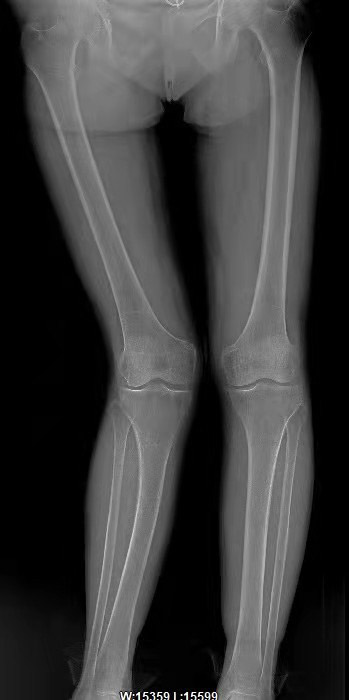

王天胜主任表示,刘女士的病例比较少见,“第一眼看她的腿怀疑膝关节会有问题,而经过X射线检查,我们发现患者的关节内结构是好的,包括间隙都很好。她腿部畸形的原因是儿时胫腓骨骨折,股骨和胫骨的畸形愈合,愈合后逐渐出现膝外翻的情况,而且角度越来愈大,达到23.5度。以至于如今疼痛无法正常走路,膝关节肿胀。那么我们首先考虑的是进行保膝矫正手术。”

患者手术前的腿部X光片